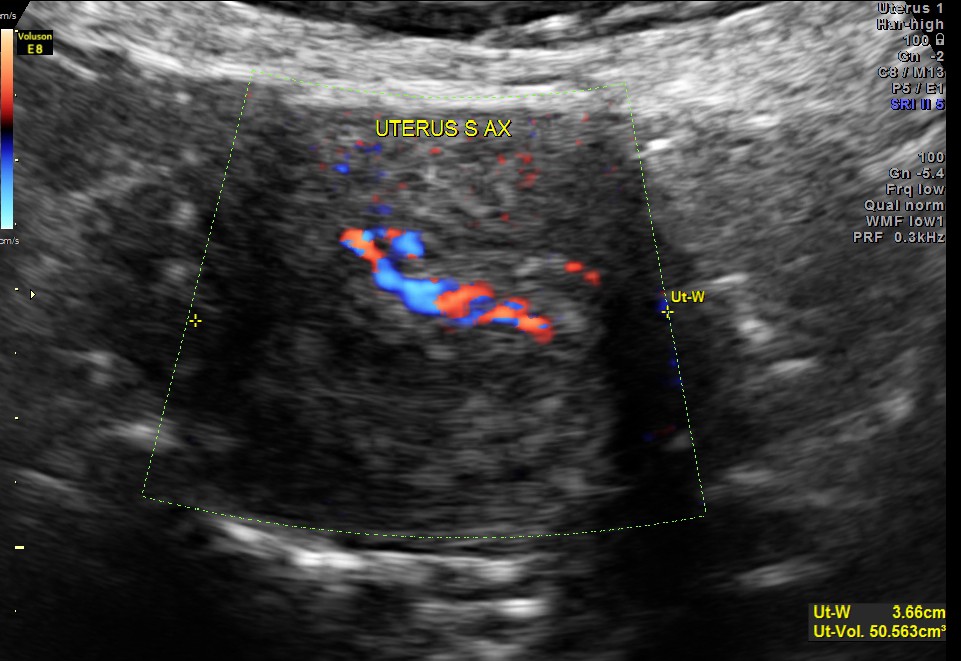

This was a 53 year old post menopausal lady who was evaluated for intermittent leucorrhoea. She had a carcinoma of breast and was operated earlier. She was on T.Tamoxifen for the past 3 years.The endometrial thickness was between 5.75 to 6.43 mms .Colour doppler showed increased vascularity.

The ovaries were normal in appearance.